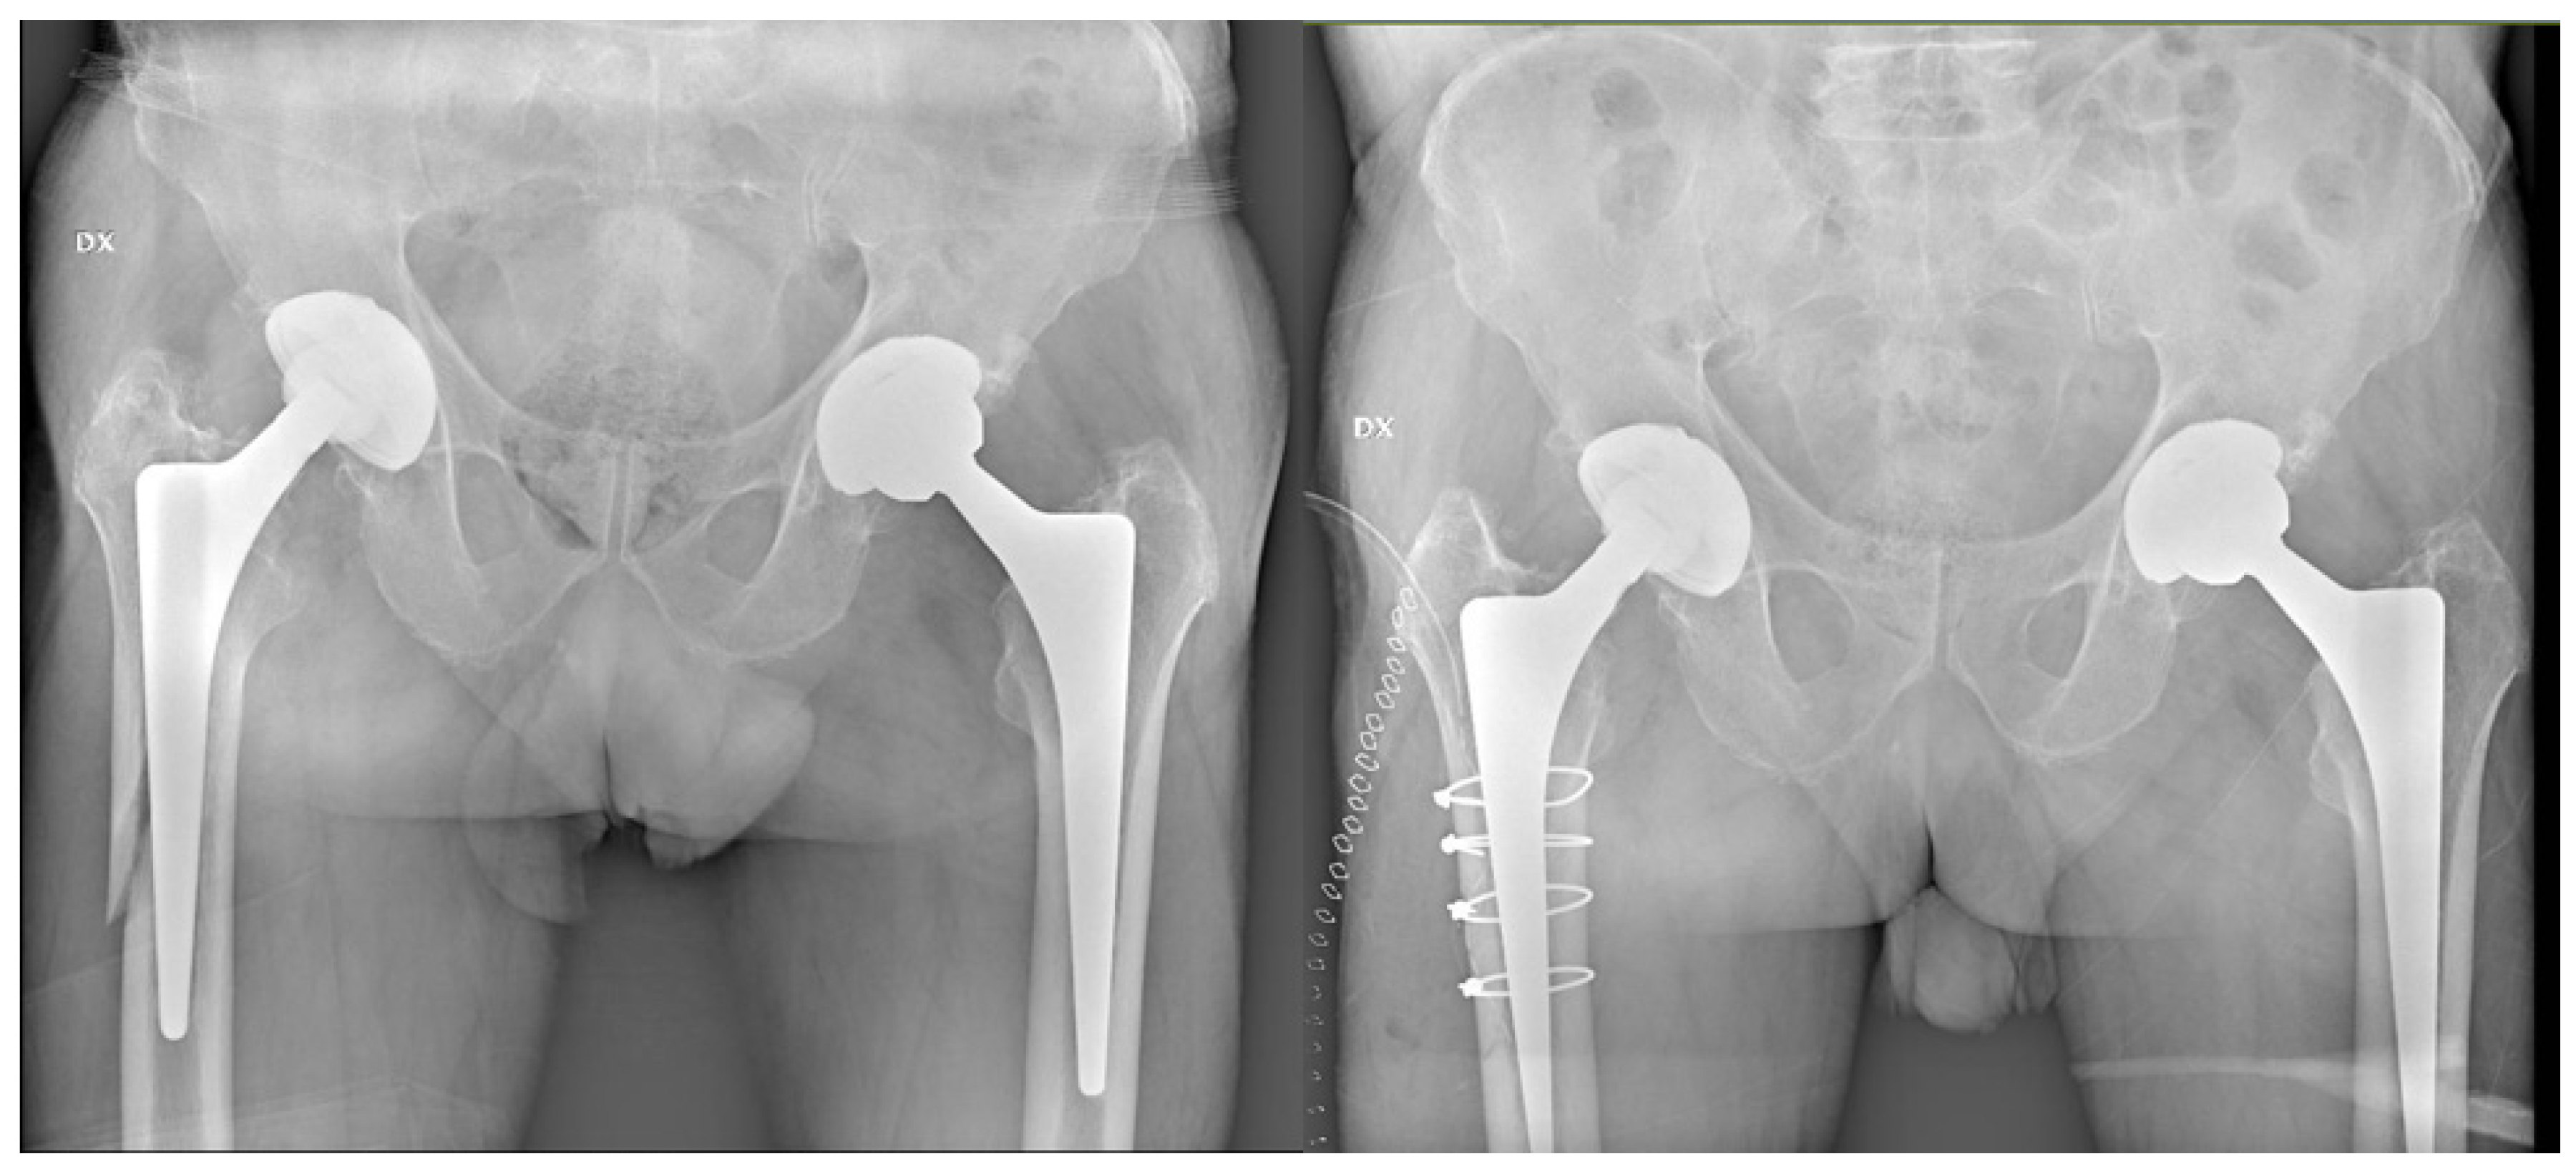

Periprosthetic Hip Fractures around the Stem: Can the Stem Design Affect Fracture Features?

2. Material and Methods

3. Results